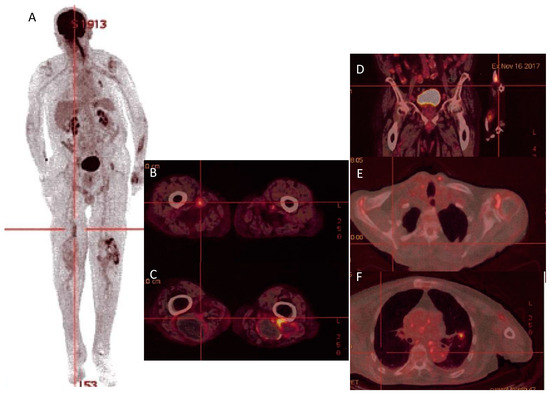

| 15 | Man/81 years old | -Serology (IF) IgGI: 1:800, IgMI: 0, IgAI: 1:100 IgGII: 1:200, IgMII: 0, IgAII: 0. | Femoro-popliteal bypass (PET-scan) | DH | -Clinical improvement -multiple hypermetabolisc foci persistence | Our case |